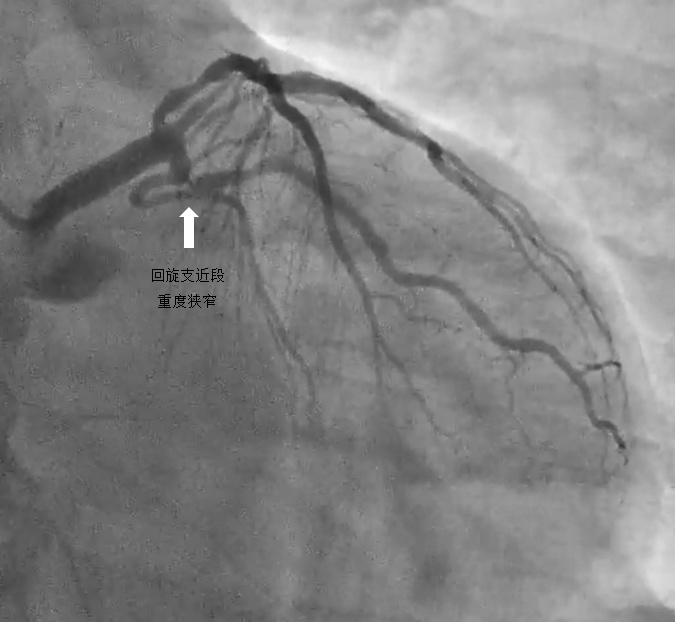

2.唐某,42岁,危险因素包括高血压、糖尿病和长期抽烟。本次因反复劳力后胸闷来我院,近期胸痛发作频繁。冠脉CT提示三支血管病变(左前降支、左回旋支重度狭窄)。

病例2

中间支的近端重度狭窄,呈次全闭塞

左回旋支近端次全闭塞

左回旋支近段使用药物球囊后,狭窄基本消失